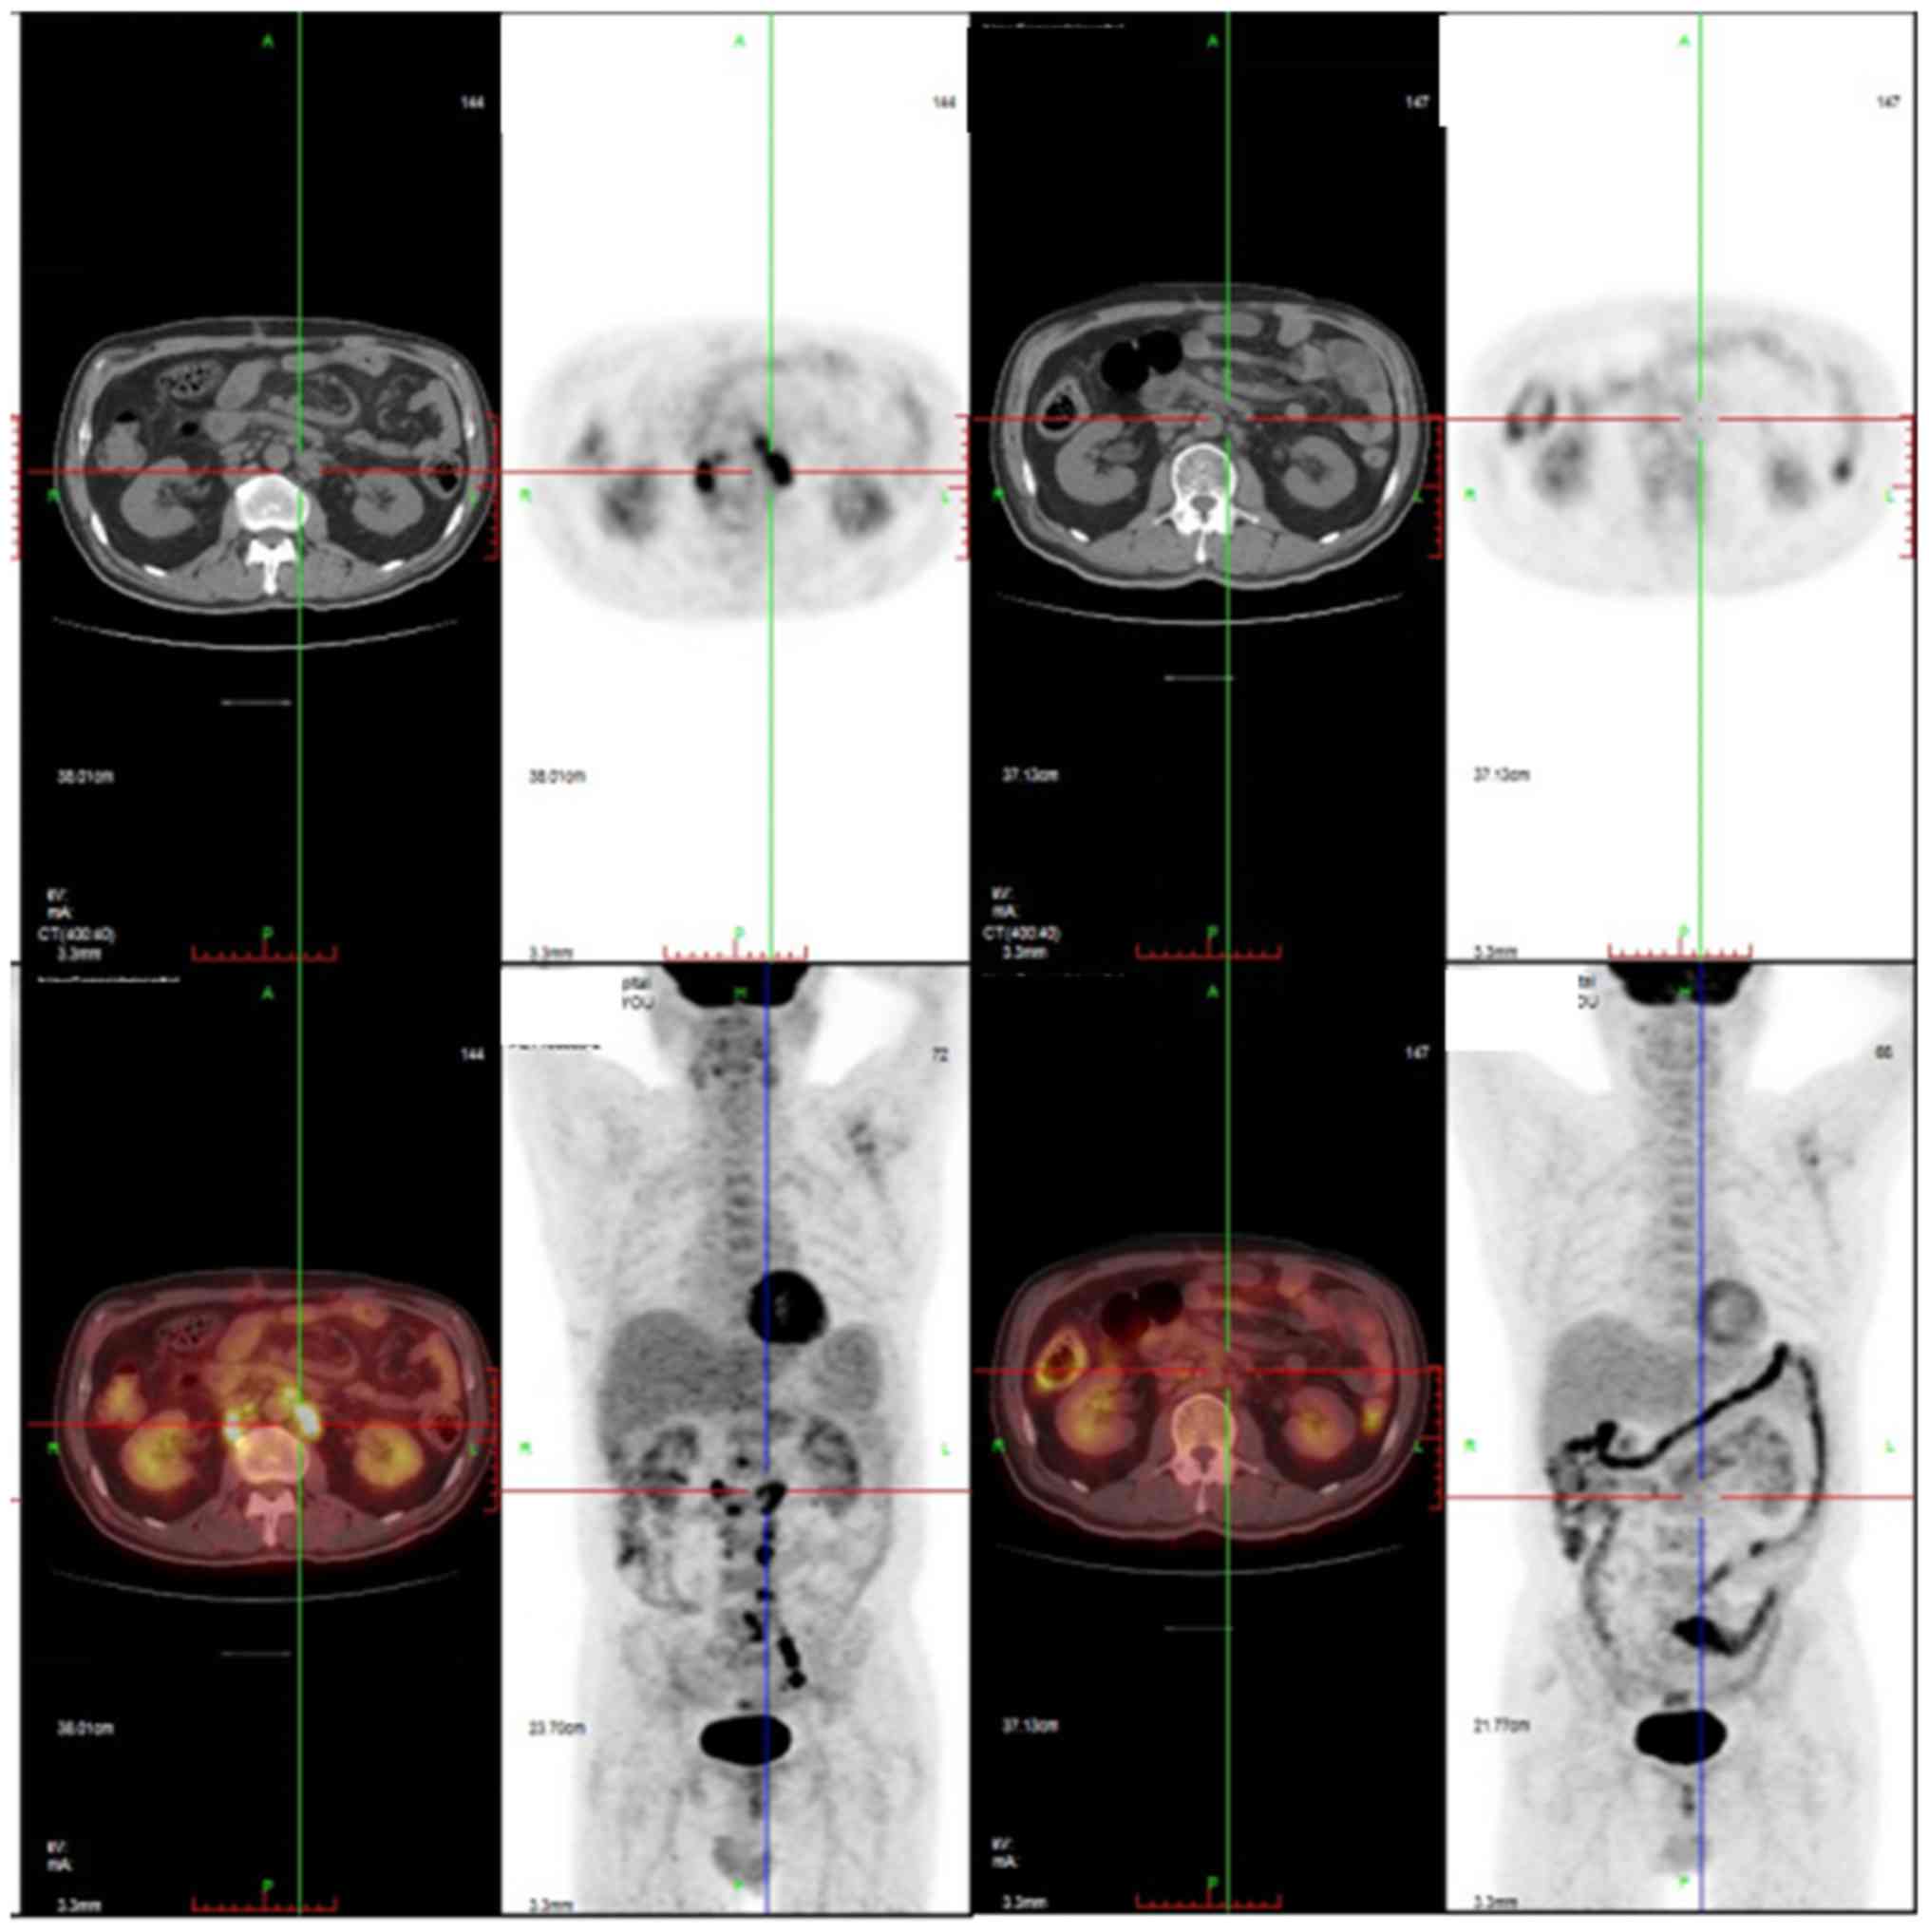

Description: Cremonini, F.